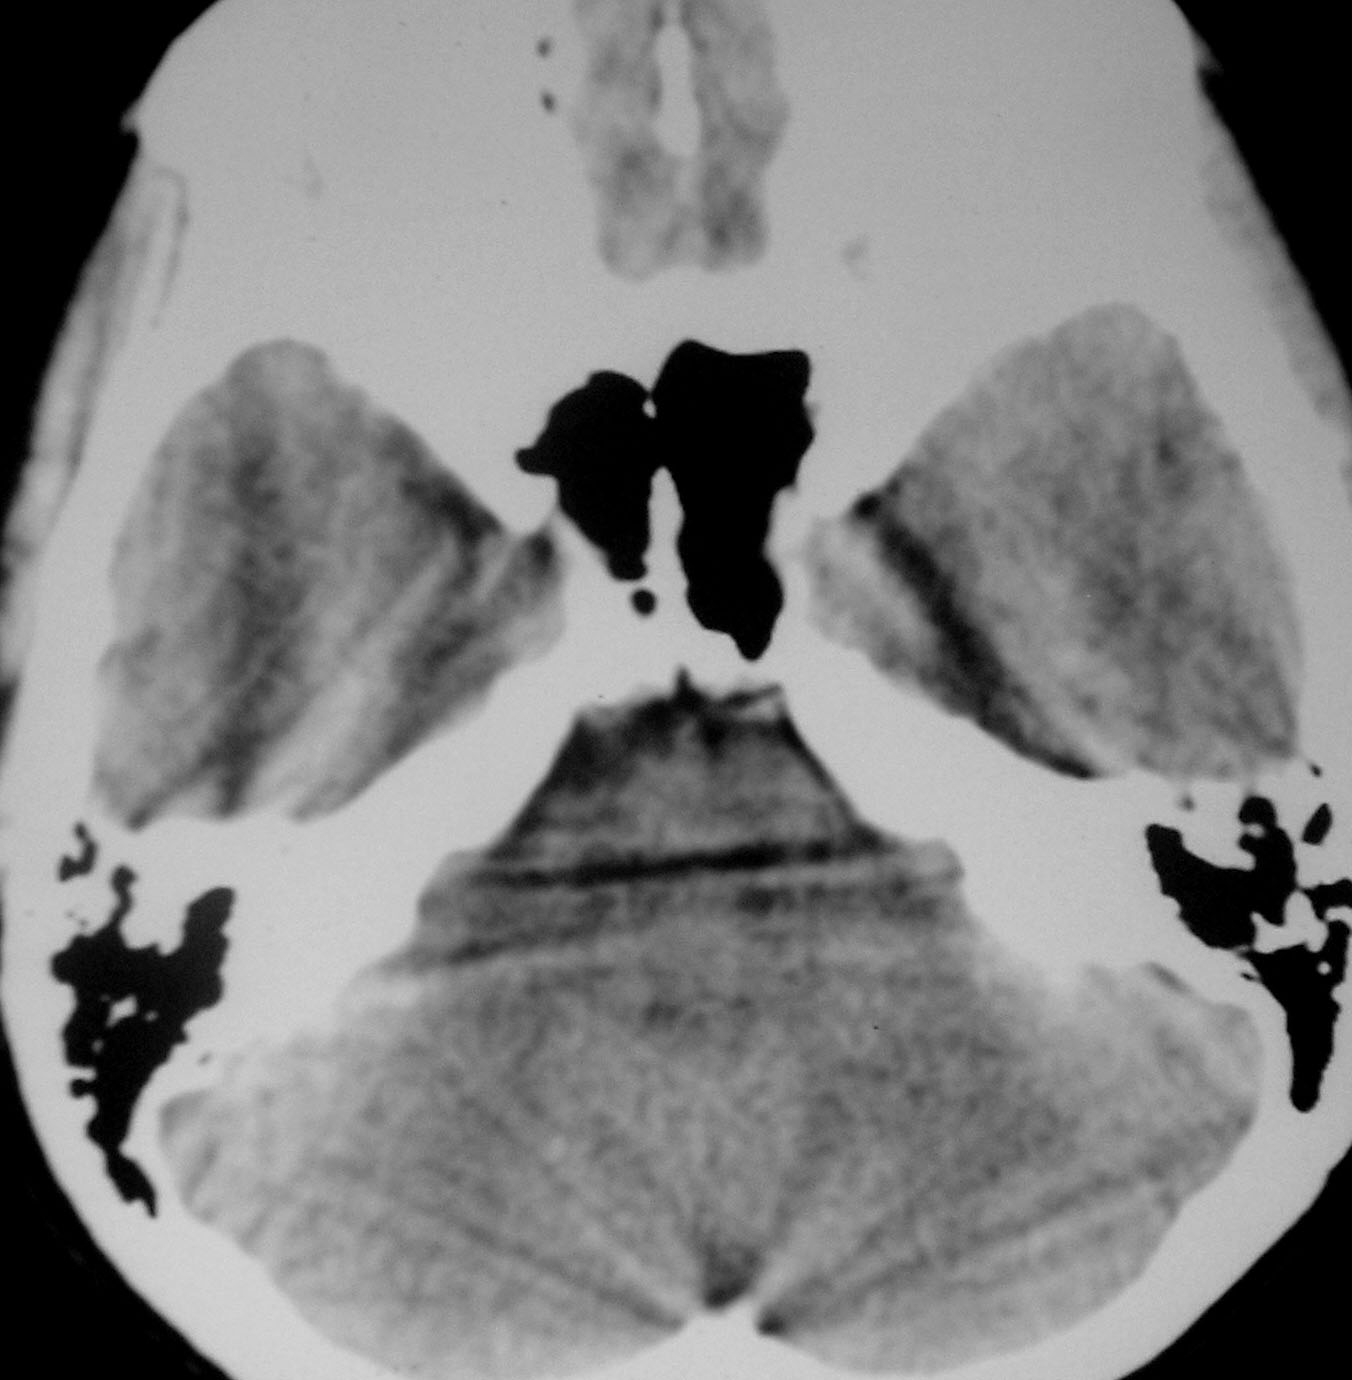

以下是引用余辉在2007-4-28 19:55:00的发言:[br]血管畸形?增强一下

以下是引用jw-830在2007-4-28 20:22:00的发言:[br]考虑血管畸形可能建议增强

以下是引用ysxyy在2007-4-29 21:14:00的发言:[br]像是假像,如果不放心可以偿试一下:[br]你用听眦线为基线扫一下,再用听眶线扫一下,就是说用不同的角度扫同一个地方;[br]看看有无变化,是不是有相同或相似的表现,即可鉴别;